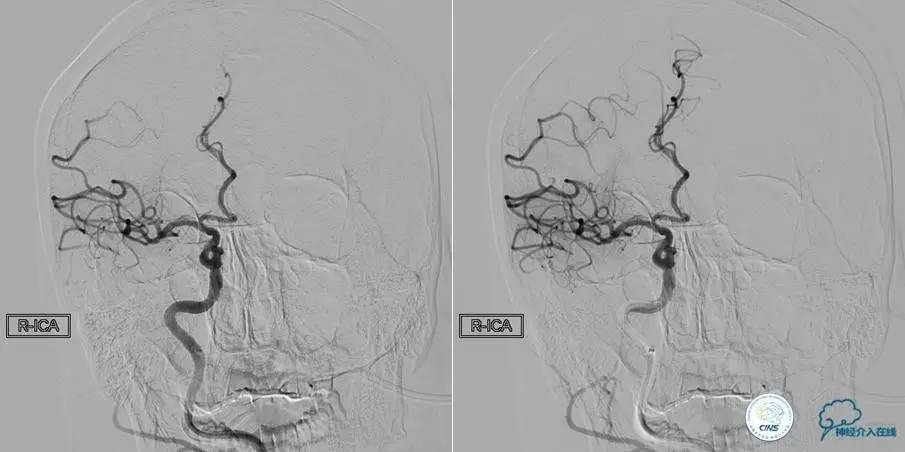

患者:徐××,男,62岁,主诉“右侧肢体活动不灵伴意识障碍3h”,于2015年6月5日入院。

患者时间窗内,发病3h开始静脉溶栓。rt-PA9mg/kg,70mg,7mgIV;63mg微量泵注入1h。期间患者症状改善不明显。观察时间后,仍无改善。遂介入交接治疗。

2015-06-05脑血管造影:左侧颈内动脉闭塞。

评估患者侧支循环,考虑患者发病时间超过6个多小时,未行血管内治疗。

▼2015-06-05颅脑MRI